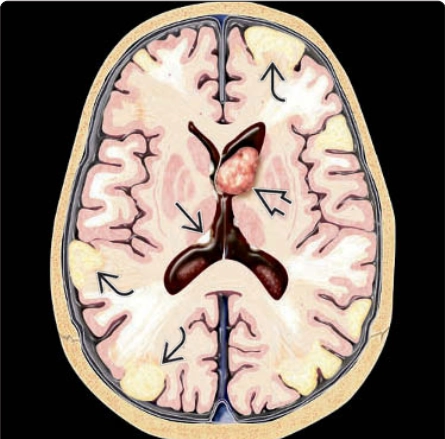

Bệnh xơ cứng củ ở thai nhi (Tuberous Sclerosis Complex - TSC)